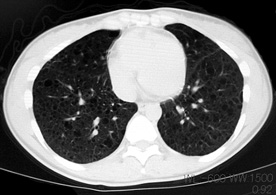

臨床的には進行性肺嚢胞化, くり返す肺気腫, 乳び性胸水貯留が特徴で, 多くの症例では進行性に呼吸不全となる*1

LAM患者さんに認められた両側肺気腫(右図:胸部CT)

初診時CT(左)から2年後のCTでは肺の嚢胞化が著明となっている。